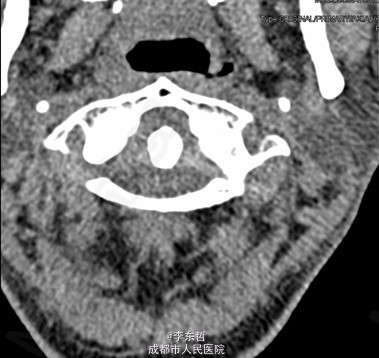

陈旧性寰枢关节脱位

患者男性,54岁,因“外伤后头颈部疼痛2年加重伴活动受限1个月”入院,自诉疼痛呈慢性起病,间歇性、反复发作并逐渐加重,为求进一步诊治故来我院,门诊以“陈旧性寰枢关节脱位”收入我科。